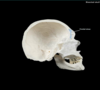

Cranium Flashcards

(33 cards)